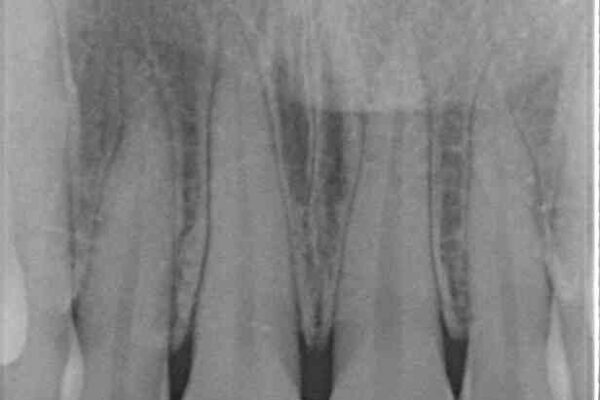

神経を取り除いたことで変色した前歯を気にして来院された患者様です。

根管治療はやり直さずに、ファイバーポストを使用した土台を植立してオールセラミッククラウンにて補綴することとしました。

治療後

• 変色した前歯をオールセラミッククラウンに 治療後画像